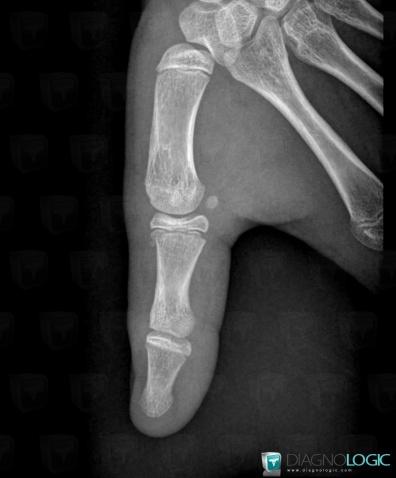

Fracture, Pouce, Radio

- Diagnostic Fracture, Localisation(s) Pouce, comportant les gammes